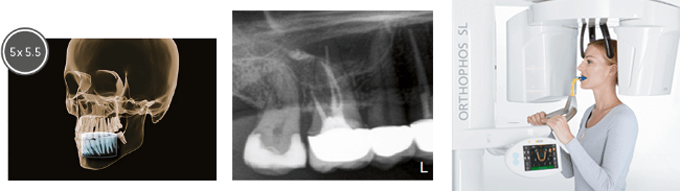

歯科用CT&セファロ

3D画像診断ができる高性能な機器です。

骨を立体的に輪切りの状態の撮影ができ、mm単位で正確な数値が計れます。

東京都杉並区の歯医者 アート歯科クリニックが導入しているCT=ORTHOPHOS SL 3Dは、11cmx10cmなどのボリュームを選択することも、 歯内治療の問題や1本のインプラント計画のために5cmx 5.5cmのボリュームを選択することも可能です。

診断に応じてボリュームサイズが選択できるため、関心領域に限局した照射で優れた画質が得れ、各治療において精密な診断・診査が可能となりました。また、CT機器デジタルレントゲンは従来のフィルムタイプに比べ、同じ人を撮影した場合でも得られる情報量が格段に多く、より鮮明な画像であるため正確な診断ができます。

そして、シロナ社のORTHOPHOS SL 3Dは、X線写真とデジタル所見とが組み合わされ、SIDEXIS 4とソフトウェア4.4からのデータが融合し、治療に理想的なデータが提供され、今まで以上に精密な治療を提供致します。

心配なX線の被爆量も、従来のフィルムタイプに比べ最大で1/10の線量で撮影が可能なので、身体にも優しいです。

CTの鮮明で正確な情報を得る事により、インプラントだけでなく、親知らずの抜歯等の治療の診断、、歯周病治療、根管治療などあらゆるシーンで診断・治療計画などに役立つ器機です。

例えば埋伏過剰歯は、多くの場合、従来のデンタルやパノラマ画像では視覚化することが非常に困難ですが、CTで3D画像にすることで、容易に正確に過剰歯の存在と隣在歯との位置関係を診査できます。

当院が導入しているCTならインプラント部位の総合的な評価と治療計画が行えます。

そして、セファロ対応なので、頭部X線規格写真で精密な診断が可能です。